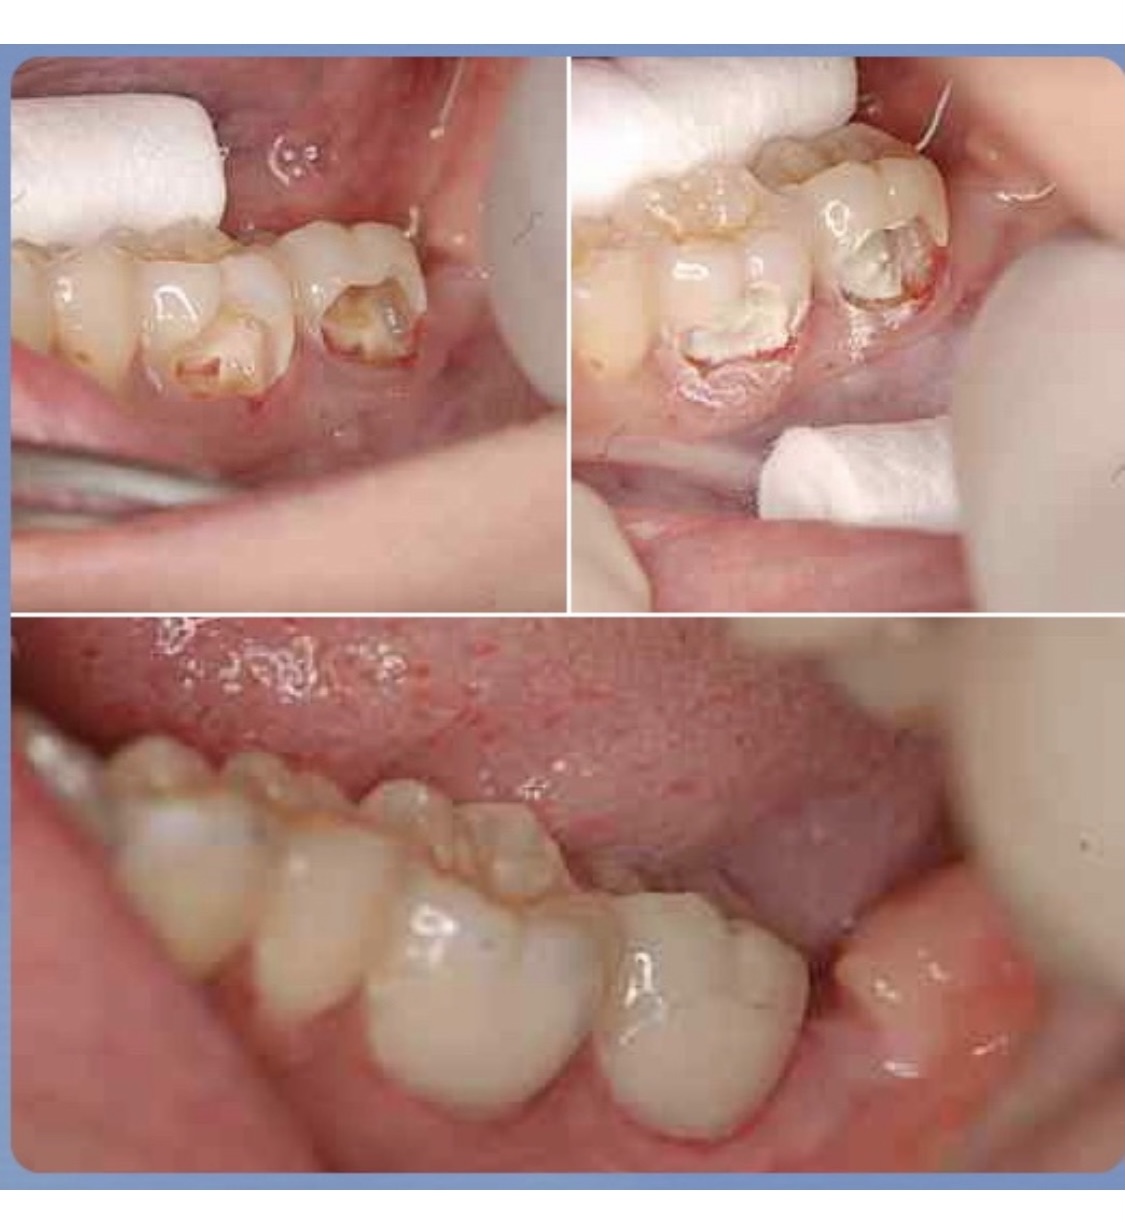

歯髄(歯の神経)をどこまで残せるか

神経を取ると歯には水分が無くなり、脆く割れ易くなってしまうため、歯はむやみに削らない、歯の神経はむやみに取らない、可及的に保存する!これがとても大切な事なのです。

歯の状態にもよりますが、すでに汚染された必要最低限の神経のみを取り除き、そこにMTAセメントというケイ酸3カルシウム主成分の材料を使って歯の神経を保存出来る場合があります。

MTAは戦後開発された歯科材料で1番の効果ある材料と言われています。保険適用外の材料にはなりますが…